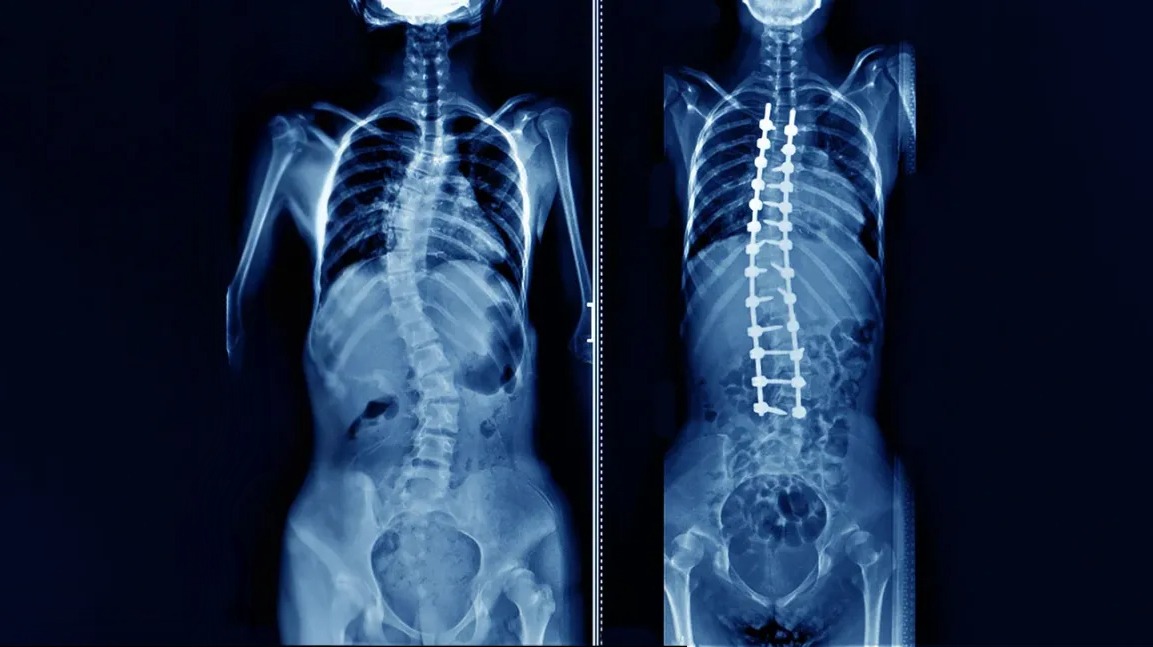

Scoliosis Surgery in Nashik for Spine Realignment ...